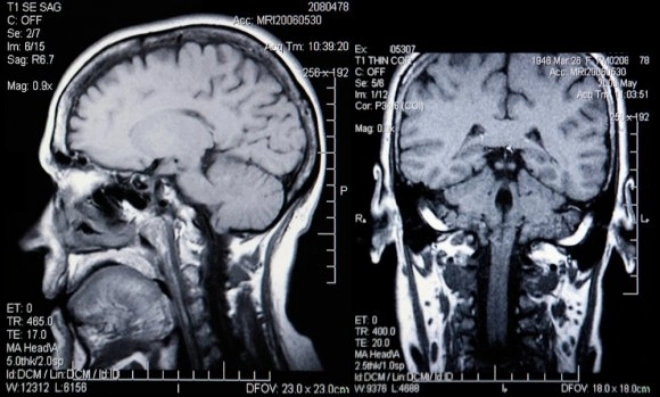

Доброякісна кіста порожнини прозорої перегородки головного мозку є досить поширеним недугою, який сьогодні можна виявити за допомогою МРТ або томографії. Серед пацієнтів з доброякісними захворюваннями головного мозку, пухлина прозорою перегородки діагностують більш ніж у 20% людей.

Визначити наявність і розміри пухлини в корі головного мозку допомагає магнітно-резонансна або комп'ютерна томографія. Такі процедури зазвичай є страхітливими для людини, проте вони не тільки нешкідливі, але і мають вирішальне значення в діагностиці кіст головного мозку . Томографія дозволяє швидко і точно виявити місце прикріплення кісти прозорого відділу головного мозку, її розміри, патогенність і масштаби впливу. Також за результатами дослідження стає ясно, чи небезпечна кіста і наскільки сильною може бути її вплив на організм.

Якщо пухлина збільшилась досить сильно і почала свій вплив на здорові ділянки головного мозку, її потрібно терміново лікувати. Спочатку процес лікування починається з діагностики МРТ головного мозку кісти прозорої перегородки і вивчення першопричин формування освіти.

Крім визначення точного місця розташування кісти прозорої перегородки МРТ дозволяє уточнити розміри пухлини, характер її впливу на сусідні тканини і приблизну швидкість росту. Додатково в рамках діагностики проводиться комплексне обстеження організму. У пацієнта беруться аналізи, вимірюється артеріальний тиск, проводяться дослідження на генетичні відхилення або хронічні захворювання, здатні надавати прямий або опосередкований вплив на швидкість росту і патогенність кісти.